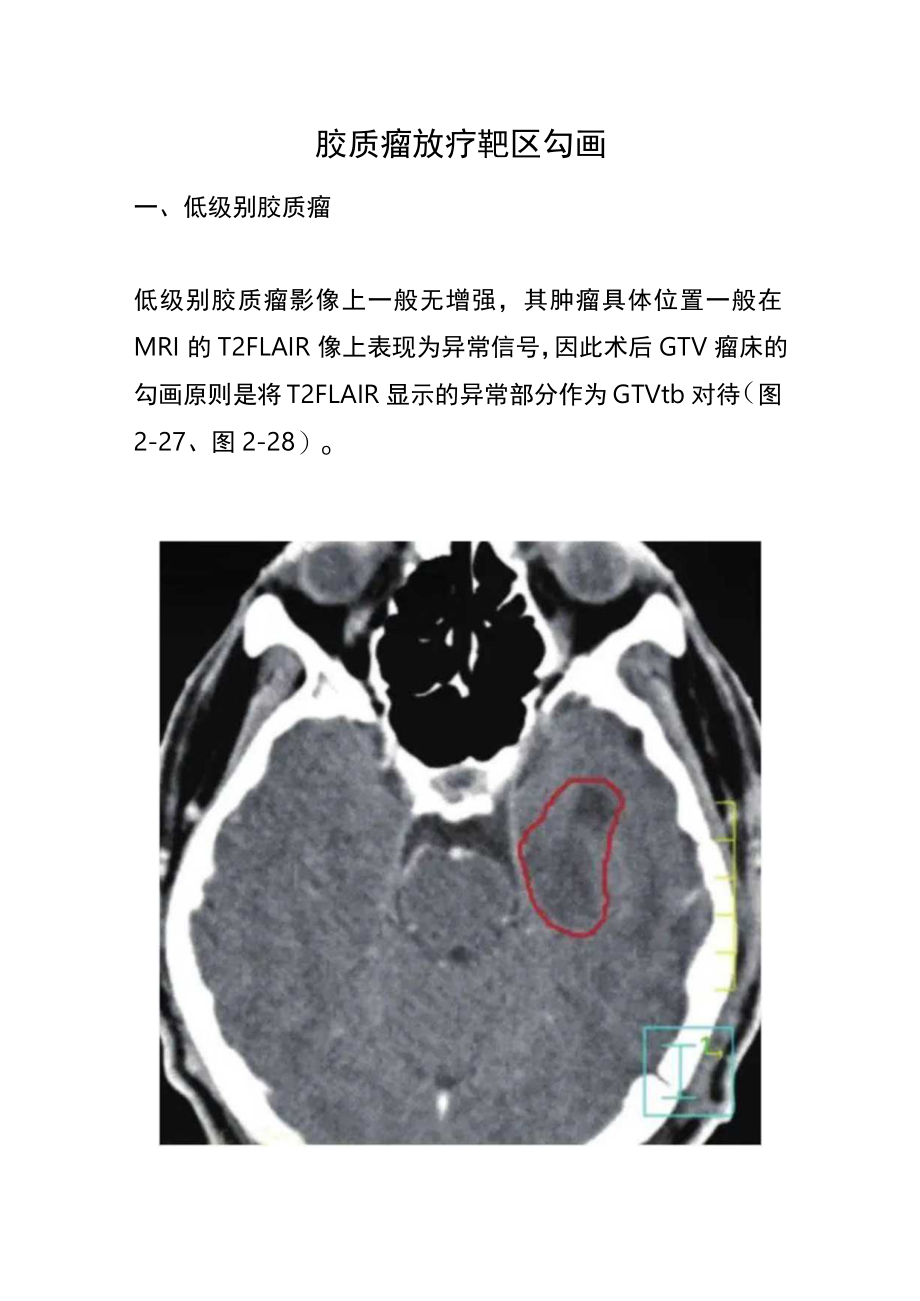

1、胶质瘤放疗靶区勾画一、低级别胶质瘤低级别胶质瘤影像上一般无增强,其肿瘤具体位置一般在MRI的T2FLAIR像上表现为异常信号,因此术后GTV瘤床的勾画原则是将T2FLAIR显示的异常部分作为GTVtb对待(图2-27、图2-28)o增强CT仅见左侧颗叶术后低密度区FLAIR显示的异常信号大于术腔图2-27口级星形细胞瘤术后GTVtb(红线)以包括FLAIR显示的异常信号为原则图2-28少突胶质瘤(II级)术后GTVtb(红线)的勾画以T2FLAIR显示的异常信号为原则,黄线为外扩1.5cm的CTV而CTv一般根据分化程度而有所不同:病理分化为I级者,CTV=GTV+1cm(即在GTV基础上外放